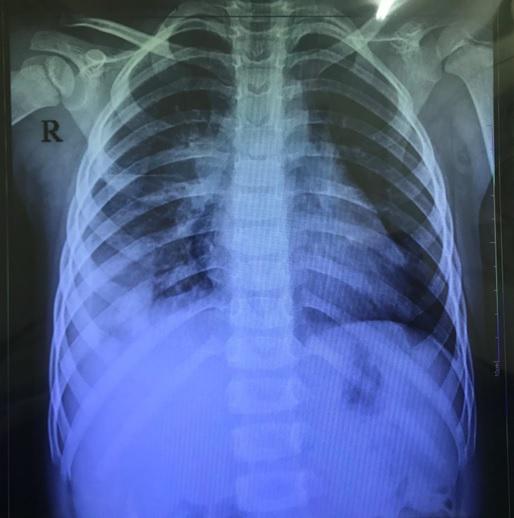

- Xét nghiệm hình ảnh: Một số xét nghiệm hình ảnh như chụp X-quang phổi hoặc siêu âm có thể được sử dụng để xác định mức độ tổn thương của màng phổi và các mô xung quanh.